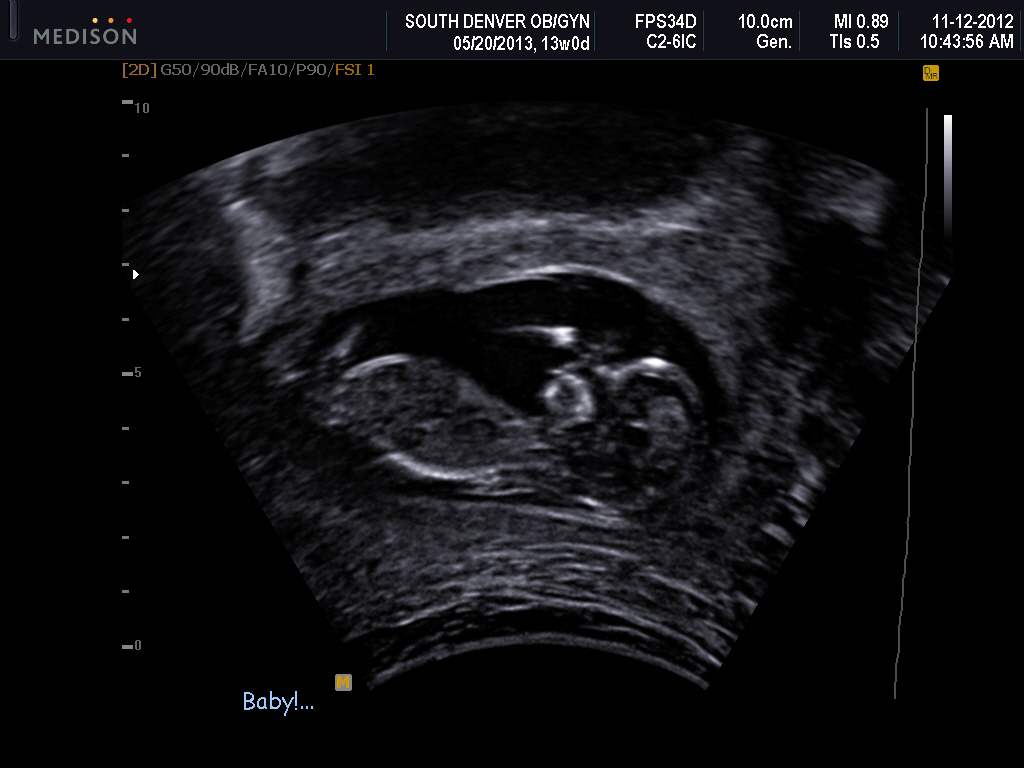

Attachment 6203Attachment 6204Attachment 6205

I had a video but not sure how to upload it. I had a potty shot on the video and I know they are not as accurate now but it sure looked like a boy. Does anybody know how to add a video?

I don't see any clues but I am very new to the nub theory. I love the image of your baby's hands. He/she looks like they are having a lot of fun in there.

I don't see a nub, but the first pic is really cute :)